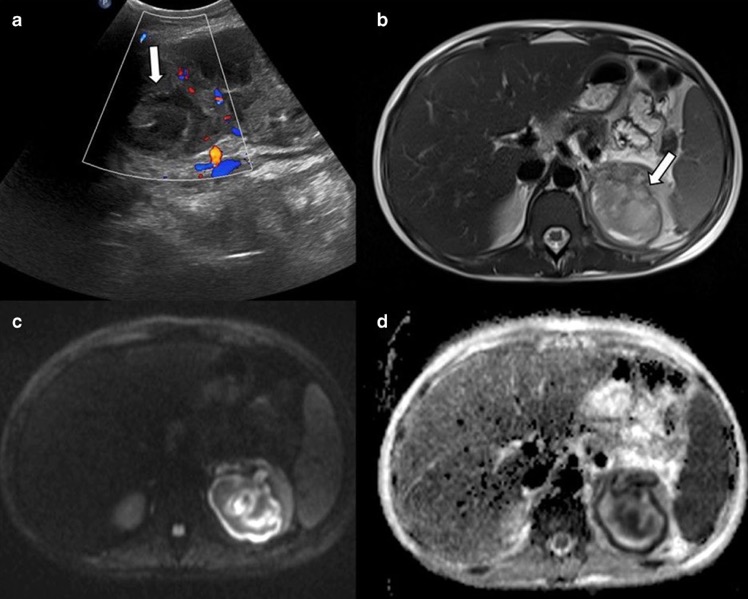

- Kyste hydatique rénal